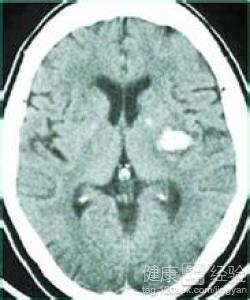

腦出血是指非外傷性腦實質內血管破裂引起的出血,是因為血管突然出現變化也導致的這種疾病,然而這種疾病是非常的危險的,如果沒有好好的處理,或者稍微的處理不當的話就會導致一些疾病出現的,比如說比較嚴重的情況下就有可能會導致心髒病,這不是不可能的,因此大家要注意一下,那麼很多人就會問了,當出現了這種情況要怎麼辦呢,要如何預防呢。